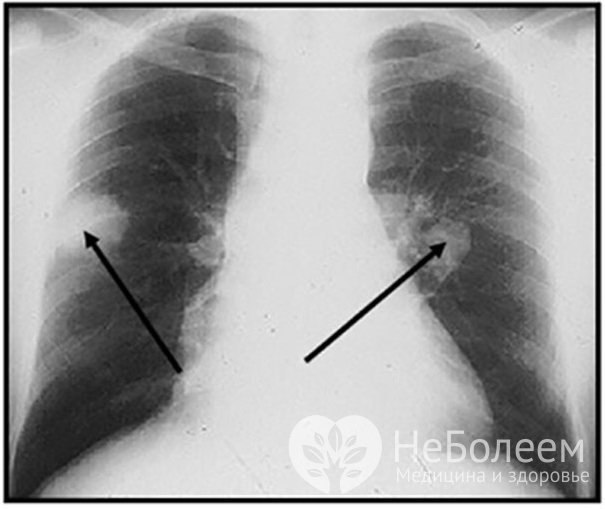

- рентгенография легких (на плевральный экссудат, полости распада, инфильтраты);

Рентгенография легких – легочные узлы при гранулематозе Вегенера

Рентгенография легких – легочные узлы при гранулематозе ВегенераПри необходимости в диагностике гранулематоза Вегенера используют и другие методы: например, компьютерную томографию или биопсию тканей верхних дыхательных путей с последующим гистологическим анализом.